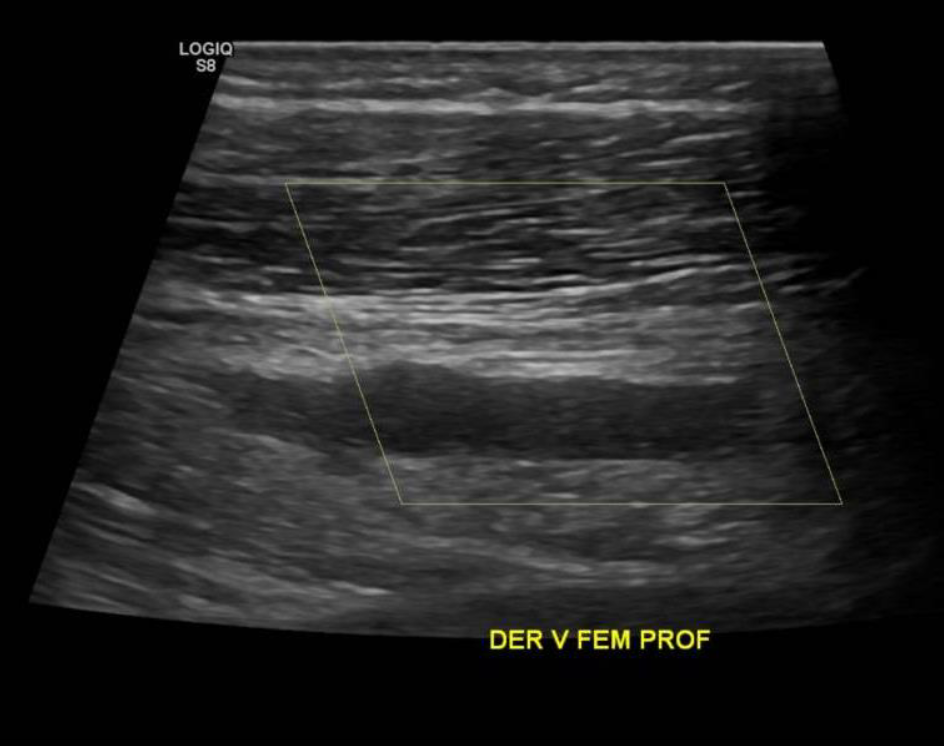

• Desde la VFC se visualiza contenido ecogénico interno, no compresible y sin señal al Doppler Color sugerente de Trombo que se extiende por toda la cara posterior del muslo comprometiendo a la Vena Femoral Profunda. Vena Femoral Superficial permeable.

Ecotomografía de Muslo Derecho

Hallazgos: Piel y tejido subcutáneo sin alteraciones. Material ecogénico endoluminal en vena femoral común, vena femoral superficial y profunda, con ausencia de flujo y compresibilidad, compatible con trombosis venosa profunda en evolución. Planos musculares de aspecto ecográfico conservado, sin evidencias de desgarros fibrilares. Engrosamiento disminución de ecogenicidad inserción proximal de los isquiotibiales, sin desgarros. No se observan lesiones nodulares ni quísticas. Contornos óseos visualizables regulares. Impresión

Diagnóstico: Hallazgos compatibles con trombosis venosa profunda de vena femoral común, vena femoral superficial y profunda. Es indispensable evaluación clínica de urgencia. Entesitis proximal de los isquiotibiales.